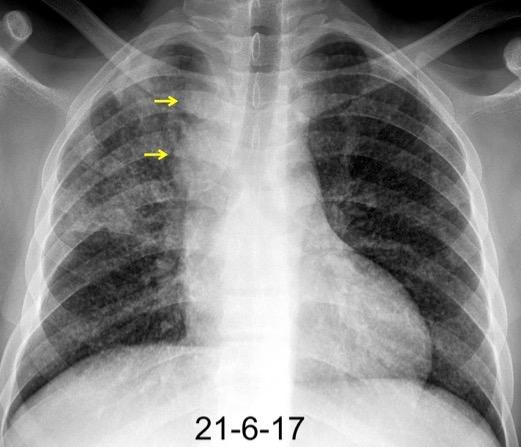

Triada de Garland

Ganglios paratraqueales derechos e hiliares bilaterales

95% de pacientes tienen ganglios hiliares bilaterales aislados o con afectación mediastínica (espec. paratraqueal derecho).

Criado E et al. Pulmonary sarcoidosis: typical and atypical manifestations at high-resolution CT with pathologic correlation. Radiographics. 2010